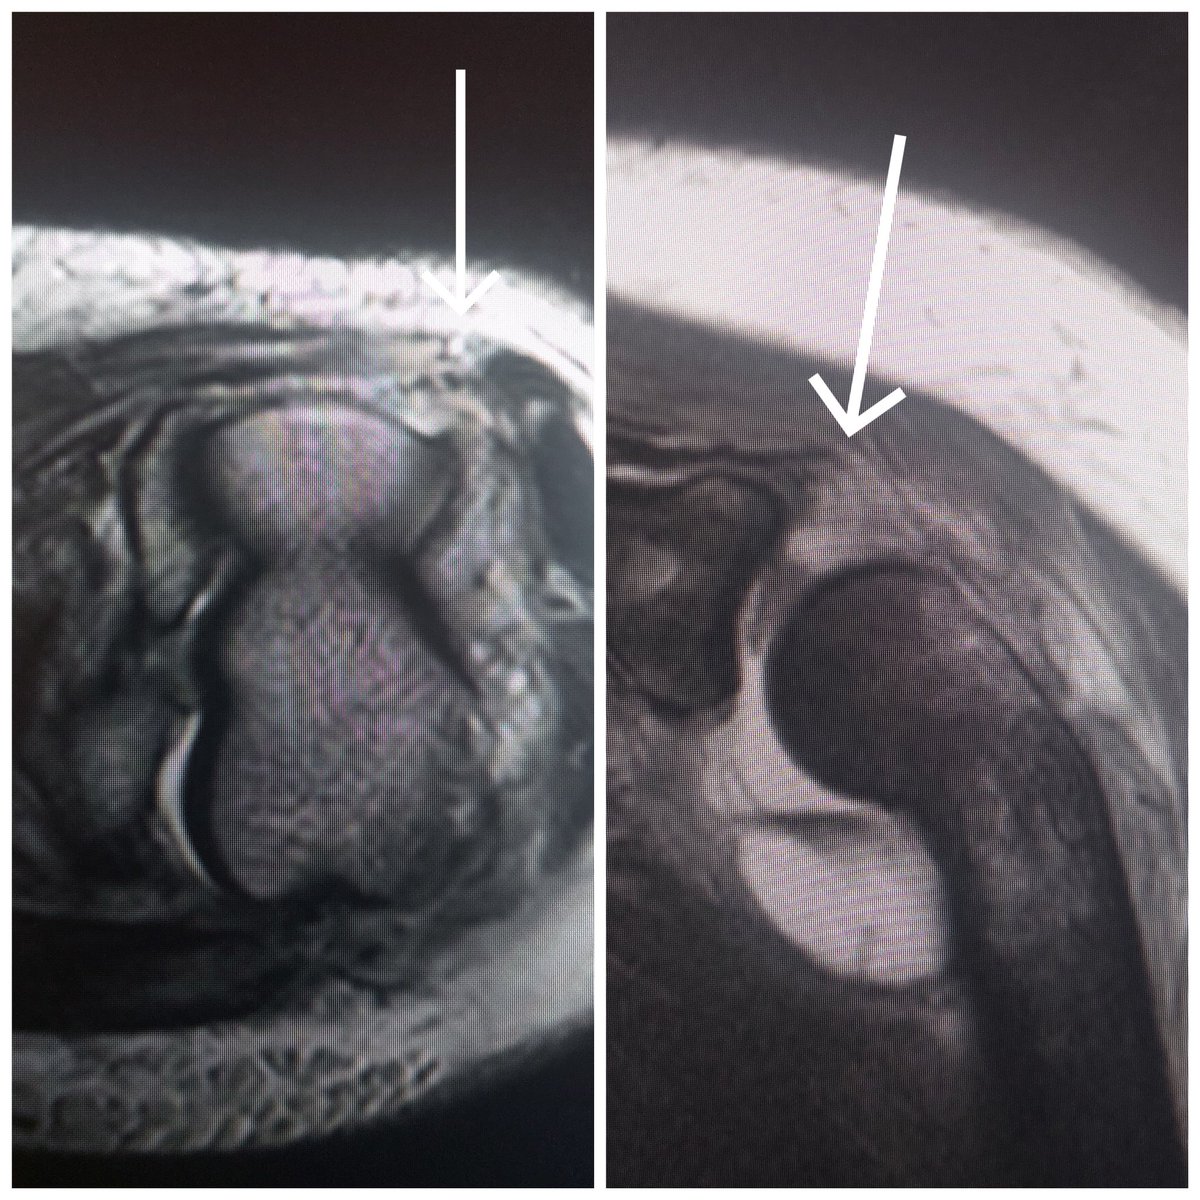

عند حدوث خلع للمفصل، يجب اجراء فحص بالرنين المغناطيسي للتأكد من سلامة الأربطة و الاوتار، كون المفصل يعتمد عليها بشكل كبير كي يبقى ثابت، و لا يعاني المريض من تلف المفصل في سن مبكر

الرنين المغناطيسي للمصاب يوضح تمزق في الأربطة الجانبية بالاضافة الى تمزق وتر العضلات القابضة و الباسطة عند مفصل المرفق